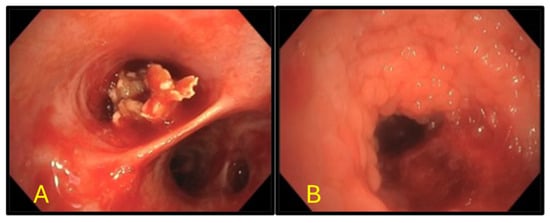

Not All PET-Avid Endobronchial Lesions Are Malignant: A Case of Chronic Foreign Body Aspiration

Background: Low-dose CT scanning is a key tool in lung cancer screening, enabling the detection of clinically significant abnormalities in asymptomatic individuals and often prompting further diagnostic evaluation. Case Presentation: We describe the case of an 80-year-old man with a heavy smoking history [...] Read more.

Background: Low-dose CT scanning is a key tool in lung cancer screening, enabling the detection of clinically significant abnormalities in asymptomatic individuals and often prompting further diagnostic evaluation. Case Presentation: We describe the case of an 80-year-old man with a heavy smoking history who was found to have a new right middle lobe collapse on screening CT. Subsequent positron emission tomography-computed tomography (PET/CT) imaging demonstrated mild fluorodeoxyglucose (FDG) uptake (SUVmax 2.7), raising concern for a low-grade endobronchial malignancy versus mucoid impaction. Flexible fiberoptic bronchoscopy revealed a large exophytic endobronchial mass occluding the airway. Histopathologic examination of the biopsy sample unexpectedly revealed vegetable material, consistent with chronic foreign-body aspiration. Discussion: Unrecognized aspiration events are relatively common in elderly adults and can mimic malignancy on imaging. This case highlights an important diagnostic pitfall: inflammatory endobronchial processes, including foreign-body granulomas, can demonstrate FDG uptake and mimic malignancy. Conclusion: Clinicians should maintain a broad differential diagnosis when evaluating PET-avid endobronchial lesions, especially in elderly patients. Full article

Show Figures

Figure 1